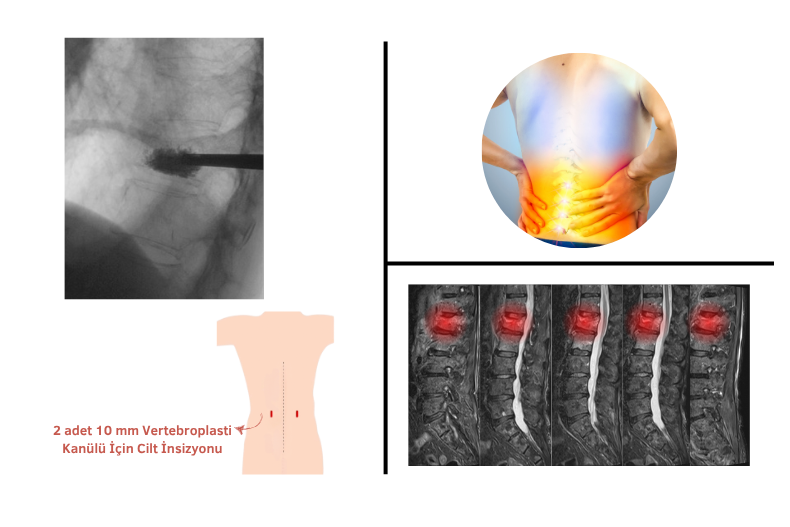

Bu tür kırıkların tedavisinde sıkça uygulanan işlemlerden biri de vertebroplasti ameliyatıdır. Bu işlemde zayıflamış veya kırılmış omura özel bir kemik çimentosu enjekte edilir. Vertebroplasti ameliyatı nasıl yapılır? Lokal veya hafif genel anestezi altında, cilt üzerinden ince bir iğne ile omur içine girilerek çimento uygulanır. İşlem genellikle 30 dakika ila 1 saat sürer. Vertebroplasti ameliyatı sonrası, hastalar genellikle aynı gün ayağa kalkabilir ve kısa sürede günlük aktivitelerine dönebilir. Ancak birkaç gün ağır kaldırmaktan kaçınmak gerekir.

Vertebroplastiye benzer bir işlem olan kifoplasti, omur içine balon yerleştirilerek çökük bölge genişletilir ve ardından kemik çimentosu uygulanır. Kifoplastinin endikasyonları, yani yapılma nedenleri arasında osteoporotik omur kırıkları, travmatik omurga çökmeleri ve bazı tümör kaynaklı omur zayıflamaları yer alır. Kemik çimentosu genellikle birkaç saat içinde sertleşir, ancak kemik dokusuna tam uyum sağlaması ve çevreyle bütünleşmesi birkaç gün sürebilir.

Kapalı ameliyatlar, küçük kesilerle yapılan, iyileşme süresi kısa ve daha az ağrılı cerrahi yöntemlerdir. Özellikle omurga hastalıklarında sıkça tercih edilir. Bel fıtığı ameliyatı, endoskopik ya da mikrocerrahiyle kapalı olarak yapılabilir. Aynı şekilde boyun fıtığı ameliyatı da küçük kesilerle sinir üzerindeki baskıyı giderir. Boyun ve belde kanal darlığı ameliyatları, daralan omurilik kanalını genişletmek için kapalı teknikle uygulanabilir. Omurga kırığı ameliyatı (vertebroplasti, kifoplasti) ise çimento enjeksiyonuyla kırık omurun güçlendirilmesini sağlar. Bel kayması ameliyatı da uygun vakalarda kapalı yöntemle, vida ve platin yerleştirilerek yapılabilir.